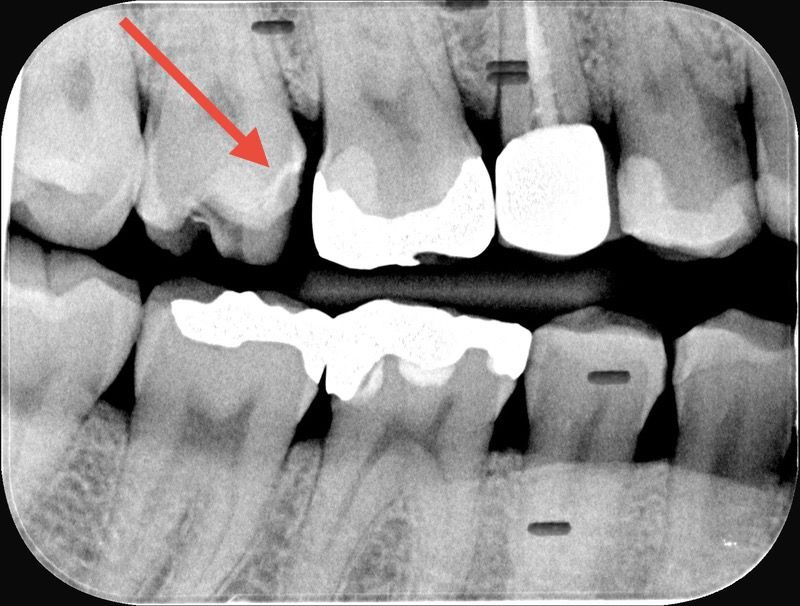

엑스레이 사진에서 어금니 충치가 의심되는지요?

엑스레이 상으로 보이는 빨간색 화살표가 가르키는 어금니 치아 인접면에서 충치가 의심되나요?

해당 어금니는 인레이 13년전에 씌웠는데 어제 인레이가 떨어져서, 재부착하기 전에 촬영한 엑스레이 사진입니다.

인레이가 떨어진 곳에 충치가 보이지는 않습니다. 인레이를 재부착하셔도 될 것으로 보입니다.

엑스레이 상으로는 충치가 잇어 보이진 않아 보입니다. 인레이가 잘 맞으면 일단 다시 접착하셔서 사용하시면될것같습니다.

해당 부분에서 치아 파절 양상이 잘 나타나 보입니다. 다만 이러한 경우 해당 부분에 약간의 충치는 존재하게 됩니다. 따라서 충치도 제거해야 할 것으로 보여집니다.

엑스레이 상에서 특별히 심한 이차우식이나 인접면 우식은 없습니다. 같은쪽 아래 어금니 2개가 오히려 이차 우식 의심됩니다.